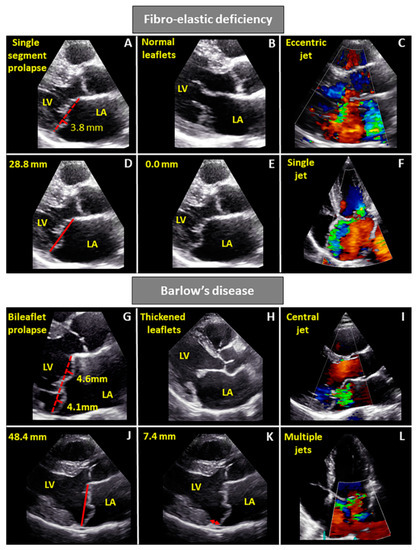

- Chandra, S.; Salgo, I.S.; Sugeng, L.; Weinert, L.; Tsang, W.; Takeuchi, M.; Spencer, K.T.; O’Connor, A.; Cardinale, M.; Settlemier, S.; et al. Characterization of degenerative mitral valve disease using morphologic analysis of real-time three-dimensional echocardiographic images: Objective insight into complexity and planning of mitral valve repair. Circ. Cardiovasc. Imaging 2011, 4, 24–32. [Google Scholar] [CrossRef]

- Clavel, M.A.; Mantovani, F.; Malouf, J.; Michelena, H.I.; Vatury, O.; Jain, M.S.; Mankad, S.V.; Suri, R.M.; Enriquez-Sarano, M. Dynamic phenotypes of degenerative myxomatous mitral valve disease: Quantitative 3-dimensional echocardiographic study. Circ. Cardiovasc. Imaging 2015, 8, e002989. [Google Scholar] [CrossRef]

| Leaflets | Single segment (usually posterior) prolapse (flail) due to chordal rupture Thickened leaflet tissue (when present) is limited to the level of the prolapsing segment Thin/normal leaflet tissue in non-prolapsing segments | Diffuse excessive valve tissue with multiple segments, bi-leaflet prolapse Thickened leaflets |

| Annulus | Normal of moderate annular dilatation No calcifications | Severe annular dilatation Calcifications could be present Mitral annular disjunction Systolic outward motion during systole (curling) |

| Chordae | Chordal rupture of the involved segment | Elongated or ruptured Thickened and/or calcified |

| Repair approach | Respect tissue (annuloplasty and neochord implantation) | Resect tissue (annuloplasty, resection and sliding, neochord implantation) |